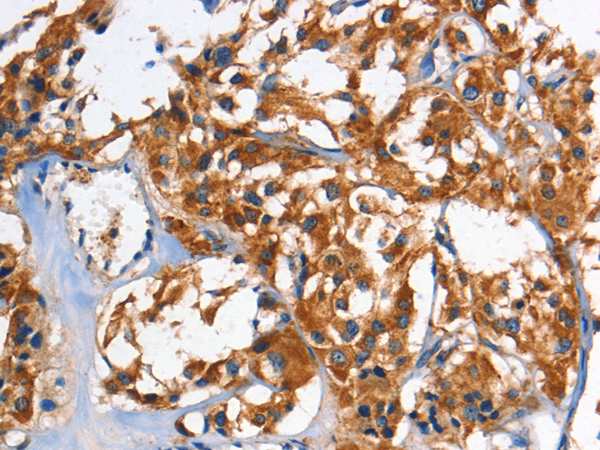

The image is immunohistochemistry of paraffin-embedded Human thyroid cancer tissue using (HK1/HK2 Antibody) at dilution 1/60.

The image is immunohistochemistry of paraffin-embedded Human lung cancer tissue using (HK1/HK2 Antibody) at dilution 1/60.